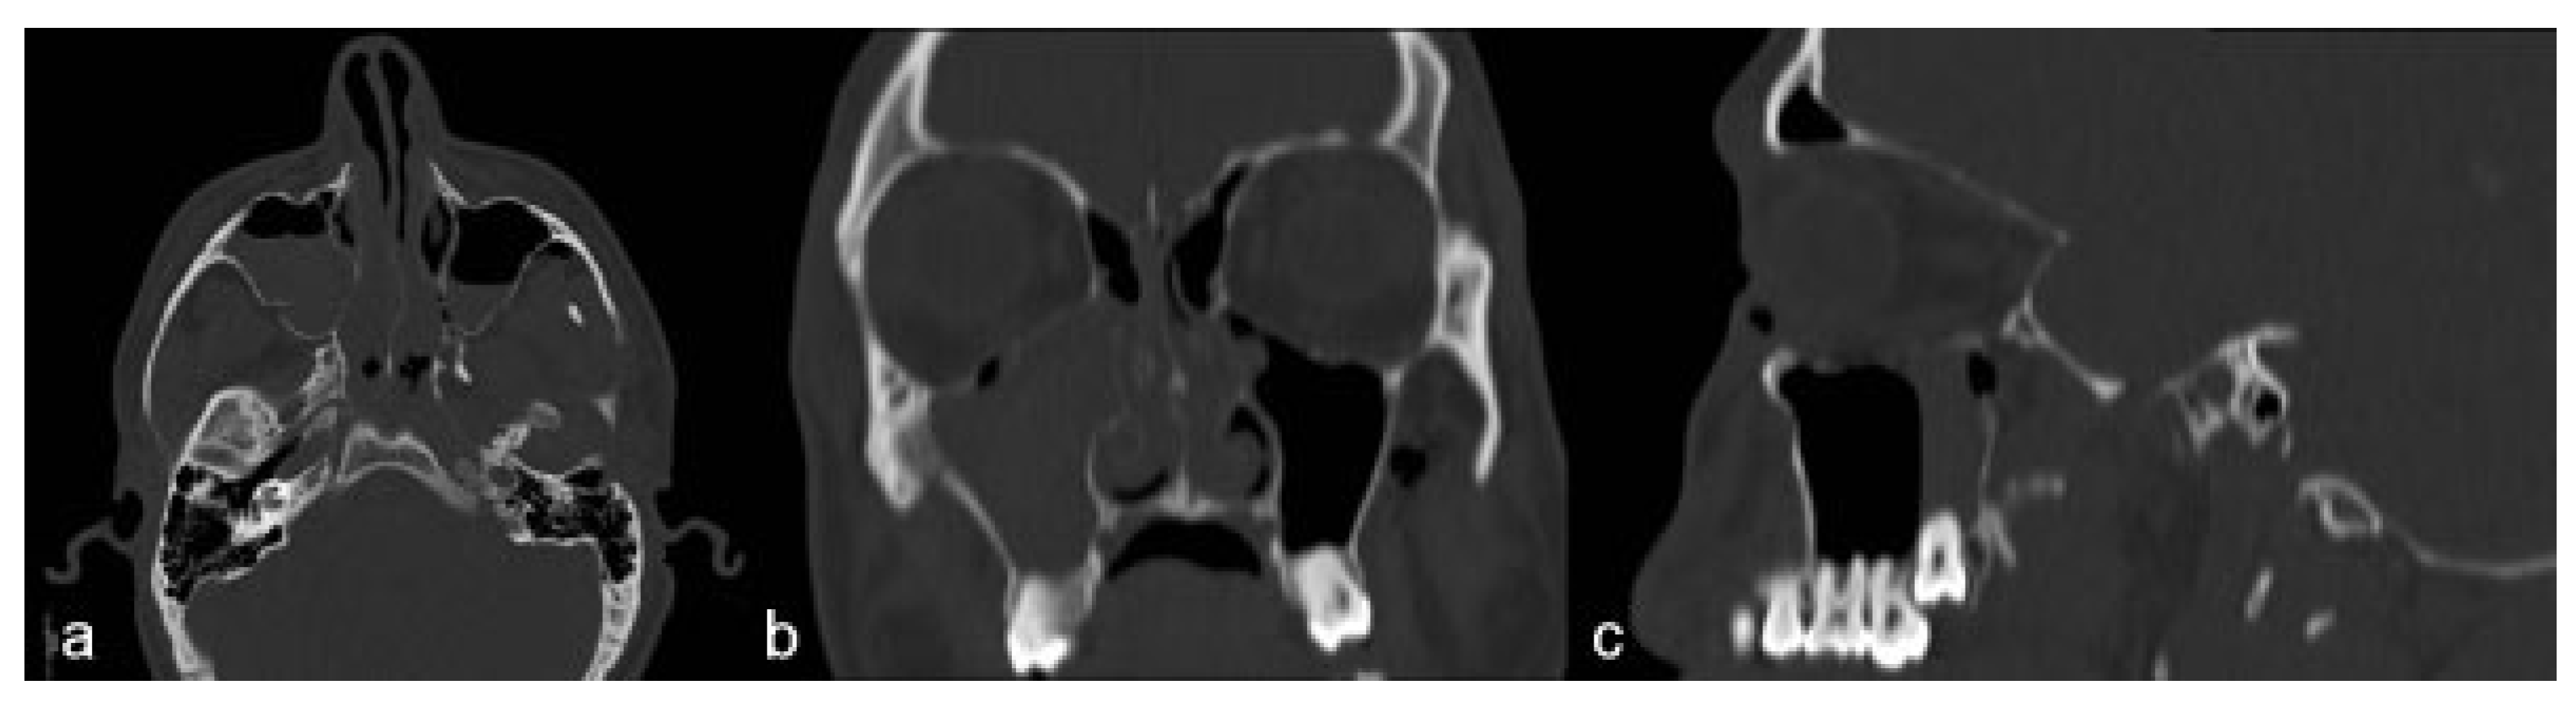

Case Report